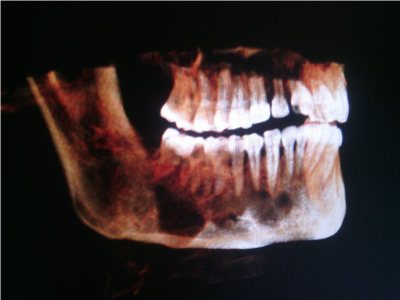

A 45-year-old Indian male patient (Figure 1) was referred to our department with a chief complaint of pain swelling in the anterior mandible for the past 4 weeks. He gave a history of trauma to the chin 2 years back. Intraoral examination revealed obliteration of vestibule from 42 to 45 and swelling in 46 and 47 region (Figure 2). The swelling was soft and tender on palpation. The overlying mucosa was slightly inflamed. No pus discharge or ooze of any kind of fluid was observed. There was no sensory loss. Panoramic radiograph (Figure 3) revealed multilocular radiolucency extending from 42 to 47, with displacement of roots of 43, 42, 41 and resorption of roots irt 43, 44, 45 was observed. A CT scan (Figure 4,5) showed resorption of buccal cortical plate in the posterior mandible. The provisional diagnosis of Ameloblastoma and keratocystic odontogenic tumor were considered. Aspiration yielded a serous brownish red colored fluid. An incisional biopsy revealed nonkeratinized stratified squamous epithelium lining with a flat interface with subsequent stroma. The epithelium shows plaque-like thickenings and whirling pattern of squamous epithelial cells. Other areas of epithelium showed pseudo-glandular pattern with few ciliated and mucus cells. Histopathology (Figure 6,7) was suggestive of glandular odontogenic cyst. Complete enucleation with removal of entire cystic lining and curettage were performed under General Anaesthesia (Figure 8,9). Primary closure was possible. Specimen was sent for histopathology, which again revealed glandular odontogenic cyst. One-year follow-up the case has revealed no recurrence.

Figure 4. Pre-operative CT scan

Figure 5. Pre-operative CT scan – Showing buccal cortex erosion